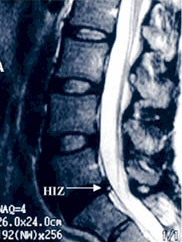

and confirm this diagnosis. Occasionally, a simple MRI

is diagnostic for this process if there is a visible

High Intensity Zone (HIZ), but most of the time it is

non-specific and further testing is needed.

presence of a High Intensity Zone (HIZ) on the MRI are

indicative of IDD.

Cases

of IDD that present with an HIZ, on MRI, are thought to

be a form of necrotizing discopathy with heightened

apoptosis of cellular elements of the disc. This is